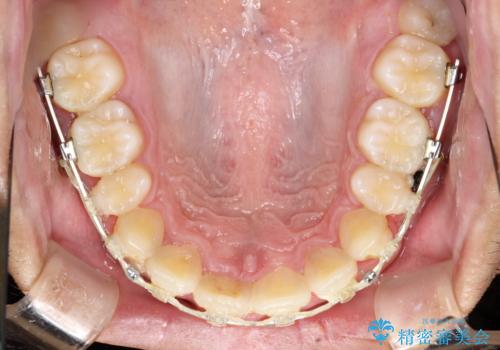

ワイヤー矯正終了時に装置除去と合わせてPMTC

- ワイヤー矯正の終了時にしばらく行っていないためクリーニングも希望されました。装置の除去j時にPMTC60分コースを行いました。

装置を除去すると、エナメル質にダメージがかかることなどがあります。除去の際、一緒にクリーニングを行うことで、エナメル質をなめらかにしたり、歯ぐきの引き締まりが見られます。また、歯ブラシだけでは取り除けない汚れも取り除きますので、歯の表面がツルツルになります。矯正治療中・終了時には合わせてPMTCを行うことがおすすめです。